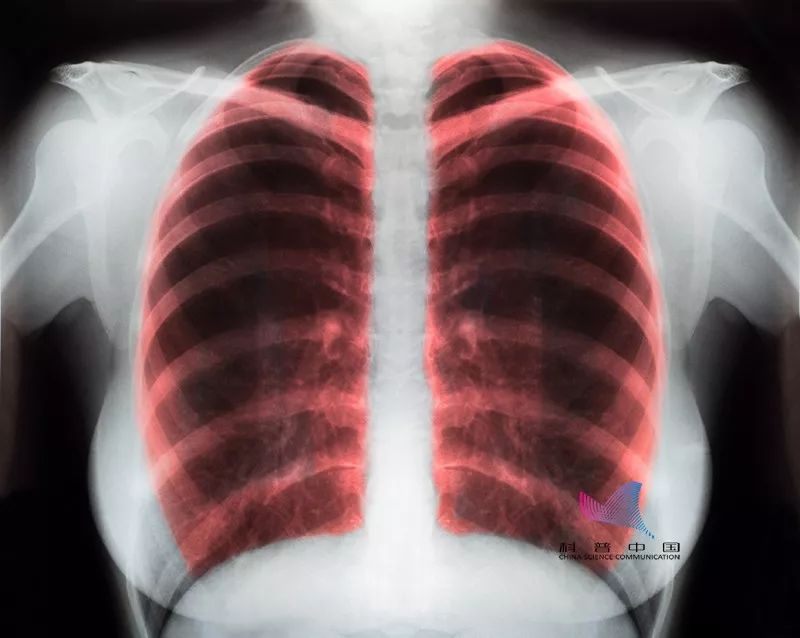

你肯定有疑问,单位每年都会组织一次体检,其中有一项就是拍胸片,为什么还是查不出肺癌的蛛丝马迹呢?

这是因为,体检当中的胸片检查,对于早期肺癌来说漏诊率很高。在正位胸片上,约43%的肺部面积与心脏、纵隔、横膈等组织重叠,一些早期肺癌难以发现。即使胸片发现肿物,也不能明确其准确位置、性质和分期等。

其实,对于肺癌高危人群而言,低剂量螺旋CT肺癌筛查可取得显著生存获益,也是目前国际唯一认可有效的肺癌筛查手段。

因为螺旋CT分辨非常高,小于4毫米结节也能够被发现,而且做一次低剂量螺旋CT扫描的辐射量近似于乘飞机飞行20小时的辐射量,对人体健康不会产生明显影响。

因此,建议对于40岁以上、常年吸烟、有肿瘤家族史的肺癌高危人群,每年做一次螺旋CT检查。如果发现异常,可进一步通过组织活检来确诊。